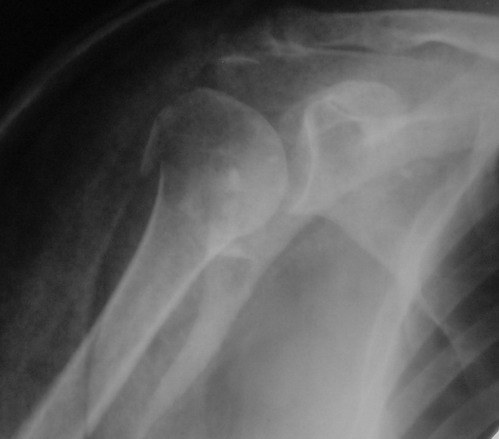

Снимки на 1-е сутки после репозиции и на 8- сутки после репозиции.

Пожалуйста